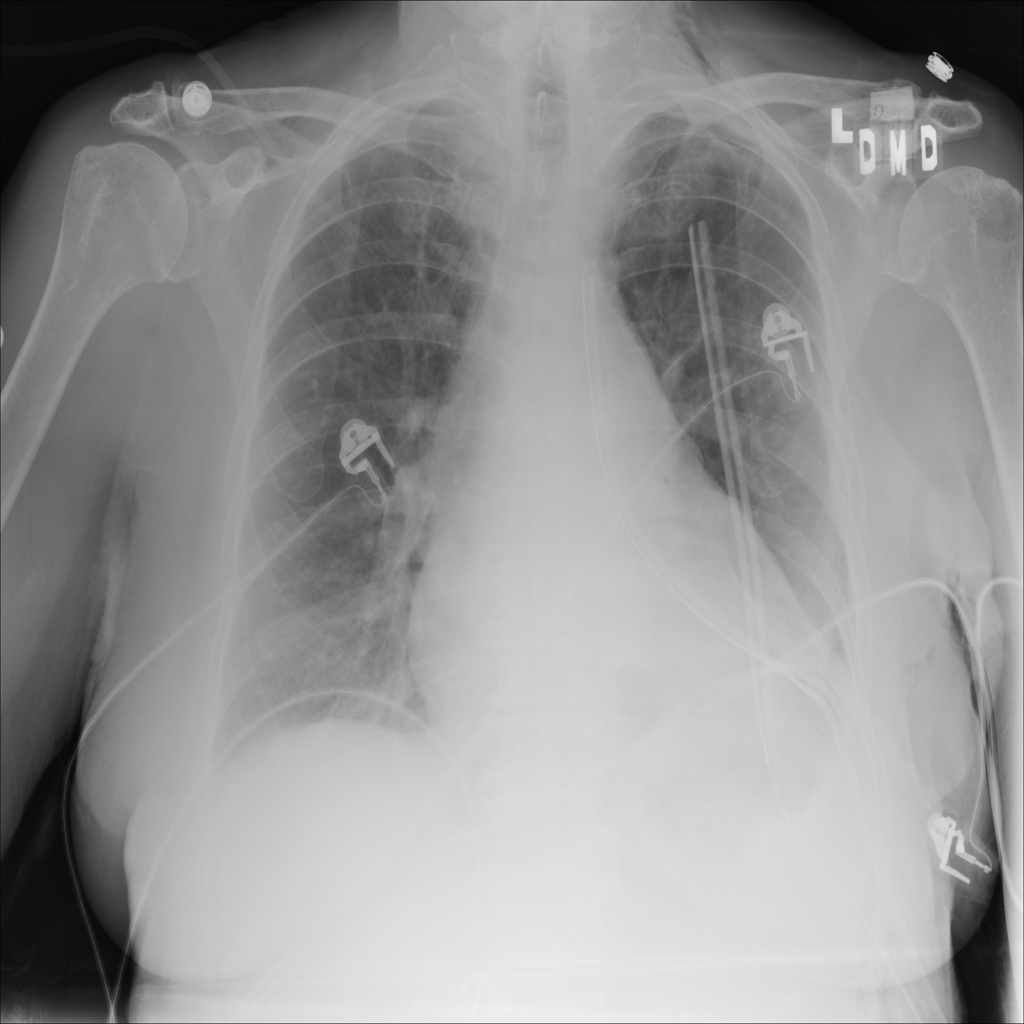

PAT-4639 · IMG-012Pneumothorax

PAT-4639 · IMG-012

AP